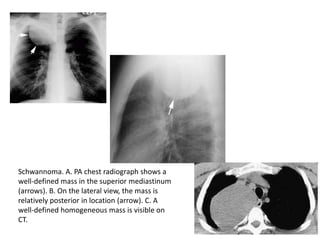

Schwannoma. A. PA chest radiograph shows a

well-defined mass in the superior mediastinum

(arrows). B. On the lateral view, the mass is

relatively posterior in location (arrow). C. A

well-defined homogeneous mass is visible on

CT.